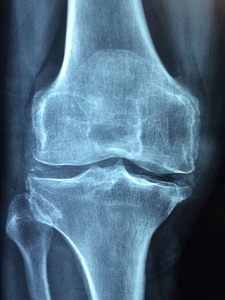

Stem cells for osteoarthritis!

I have several patients waiting for this one. A small study in Canada has demonstrated significant improvement over a year with a dozen patients having stem cells removed from their own bone marrow injected into their arthritic knees. Both subjective improvements, MRI results and inflammation marker studies show decreased arthritis and rebuilding of knee cartilage.